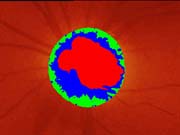

Očekávali byste protažení exkavace k hornímu pólu terče, jak nám ukazuje tento snímek z tomografu HRT II.

exkavace levé oko

Na kterém oku je exkavace větší, na pravém nebo na levém? Podle pohledu na fotografie jistě na levém.

Co je příčinou toho, že při pohledu na snímky hodnotíme rozsah exkavace nesprávně? Je to skutečnost, že i růžová oblast neuroretinálního lemu může být již prohloubená, což vídáme zvláště na počátku rozvoje glaukomové neuropathie.

A jak se můžeme vyhnout záměně okrsku bledší barvy za skutečnou exkavaci? Tím, že budeme mít na paměti, že exkavace může být větší než nablednutí. Také zařazení zeleného filtru na pomůže snížit nežádoucí barevný kontrast.